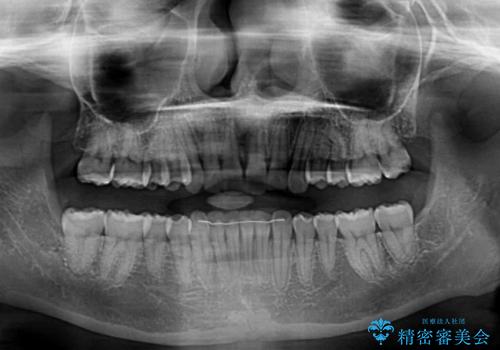

- 前歯のデコボコ気になるとのことで来院された患者様です。

下顎骨が上顎骨に対して右側にシフトしており、さらに下顎が後方に位置しているため、非常に強い咬合力で食いしばっている状態でした。

上下顎ともに歯列全体の後方移動とIPR(歯と歯の間を削る)によってデコボコが解消するように設計し、インビザラインにより治療を行うこととしました。

強い咬合力による臼歯部の噛みにくさと、それに伴う歯の移動の鈍さに悩まされ、非常に長い期間を要することとなりました。

上下正中位置は、治療開始時よりは改善したものの、ここが限界であろうというところでのゴールとなりました。

下顎前歯の大半が隠れている状態ですが、左右への歯ぎしりはスムーズに行うことができ、就寝時には後戻り防止も兼ねて、食いしばり対策としてマウスピースの使用を継続するようお願いしております。